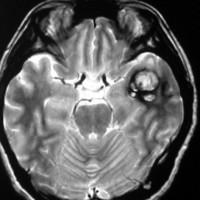

海綿状血管腫はMRIの撮影条件によっていろいろな見え方をします

腫瘍から少し出血したために,患者さんはけいれん(てんかん発作)を起こしました。左のT1強調画像では出血を疑います。中央のT2強調画像では海綿状血管腫の周りに脳浮腫があるために白くぼやけた部分があります。右の造影剤を使ったMRIでは造影剤が入るところがほどんど無いことがわかります。側頭葉の海綿状血管腫は側頭葉てんかんという症状で発症することが多いです。

出血が溶けて少し小さくなっています。海綿状血管腫の周りには黒い縁取りがあります。この黒い部分は血液が溶けて残った鉄が脳の中にたまったことを示しています(siderosisといいます)。この鉄のしみ込みはけいれんの原因になると考えられます。この海綿状血管腫は中等度の大きさですが,治療が難しいほどのてんかんが無ければ手術などしないでほっておいてもいいです。手術で側頭葉(特に海馬)を損傷すると記憶の障害などもでます。